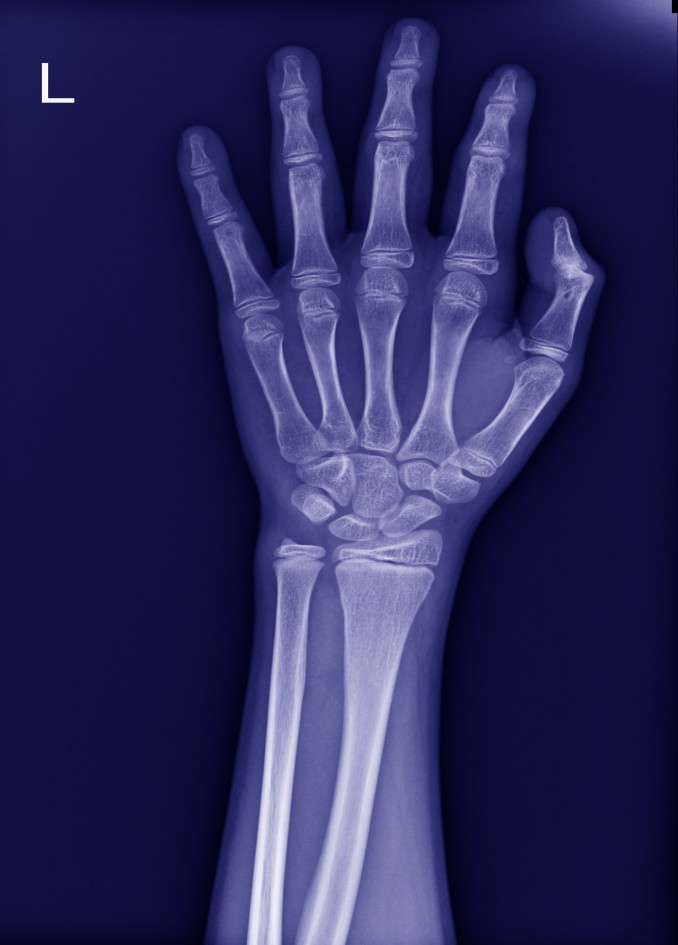

X-ray 사진을 찍어보면, 검게 보이던 성장판이 사라지고 뼈가 하나로 붙은 것처럼 보입니다. 왼쪽의 사진은 실제 제 아이의X-ray 사진입니다. 빨간색 네모 부분이 성장판입니다. 공간이 벌어져있고 얇은 판 같은 금이 보입니다. 하지만 그 옆의 사진은 뼈가 하나로 길게 연결되어 있습니다. 이렇듯 성장판이 모두 뼈로 바뀌고 더 이상 뼈 양 끝에 물렁한 연골이 사라지면 이를두고 '성장판이 닫혔다'고 표현합니다.

방사선 검사상 뼈를 비교해보아 알게 되는 나이입니다. 왼손과 손목의 X-선 촬영을 하고 골 성숙도를 비교하여 측정하는 것입니다. 뼈나이를 통해 현재 성장기의 어느 부분에 도달했는지와 앞으로의 계획을 세울수 있습니다.